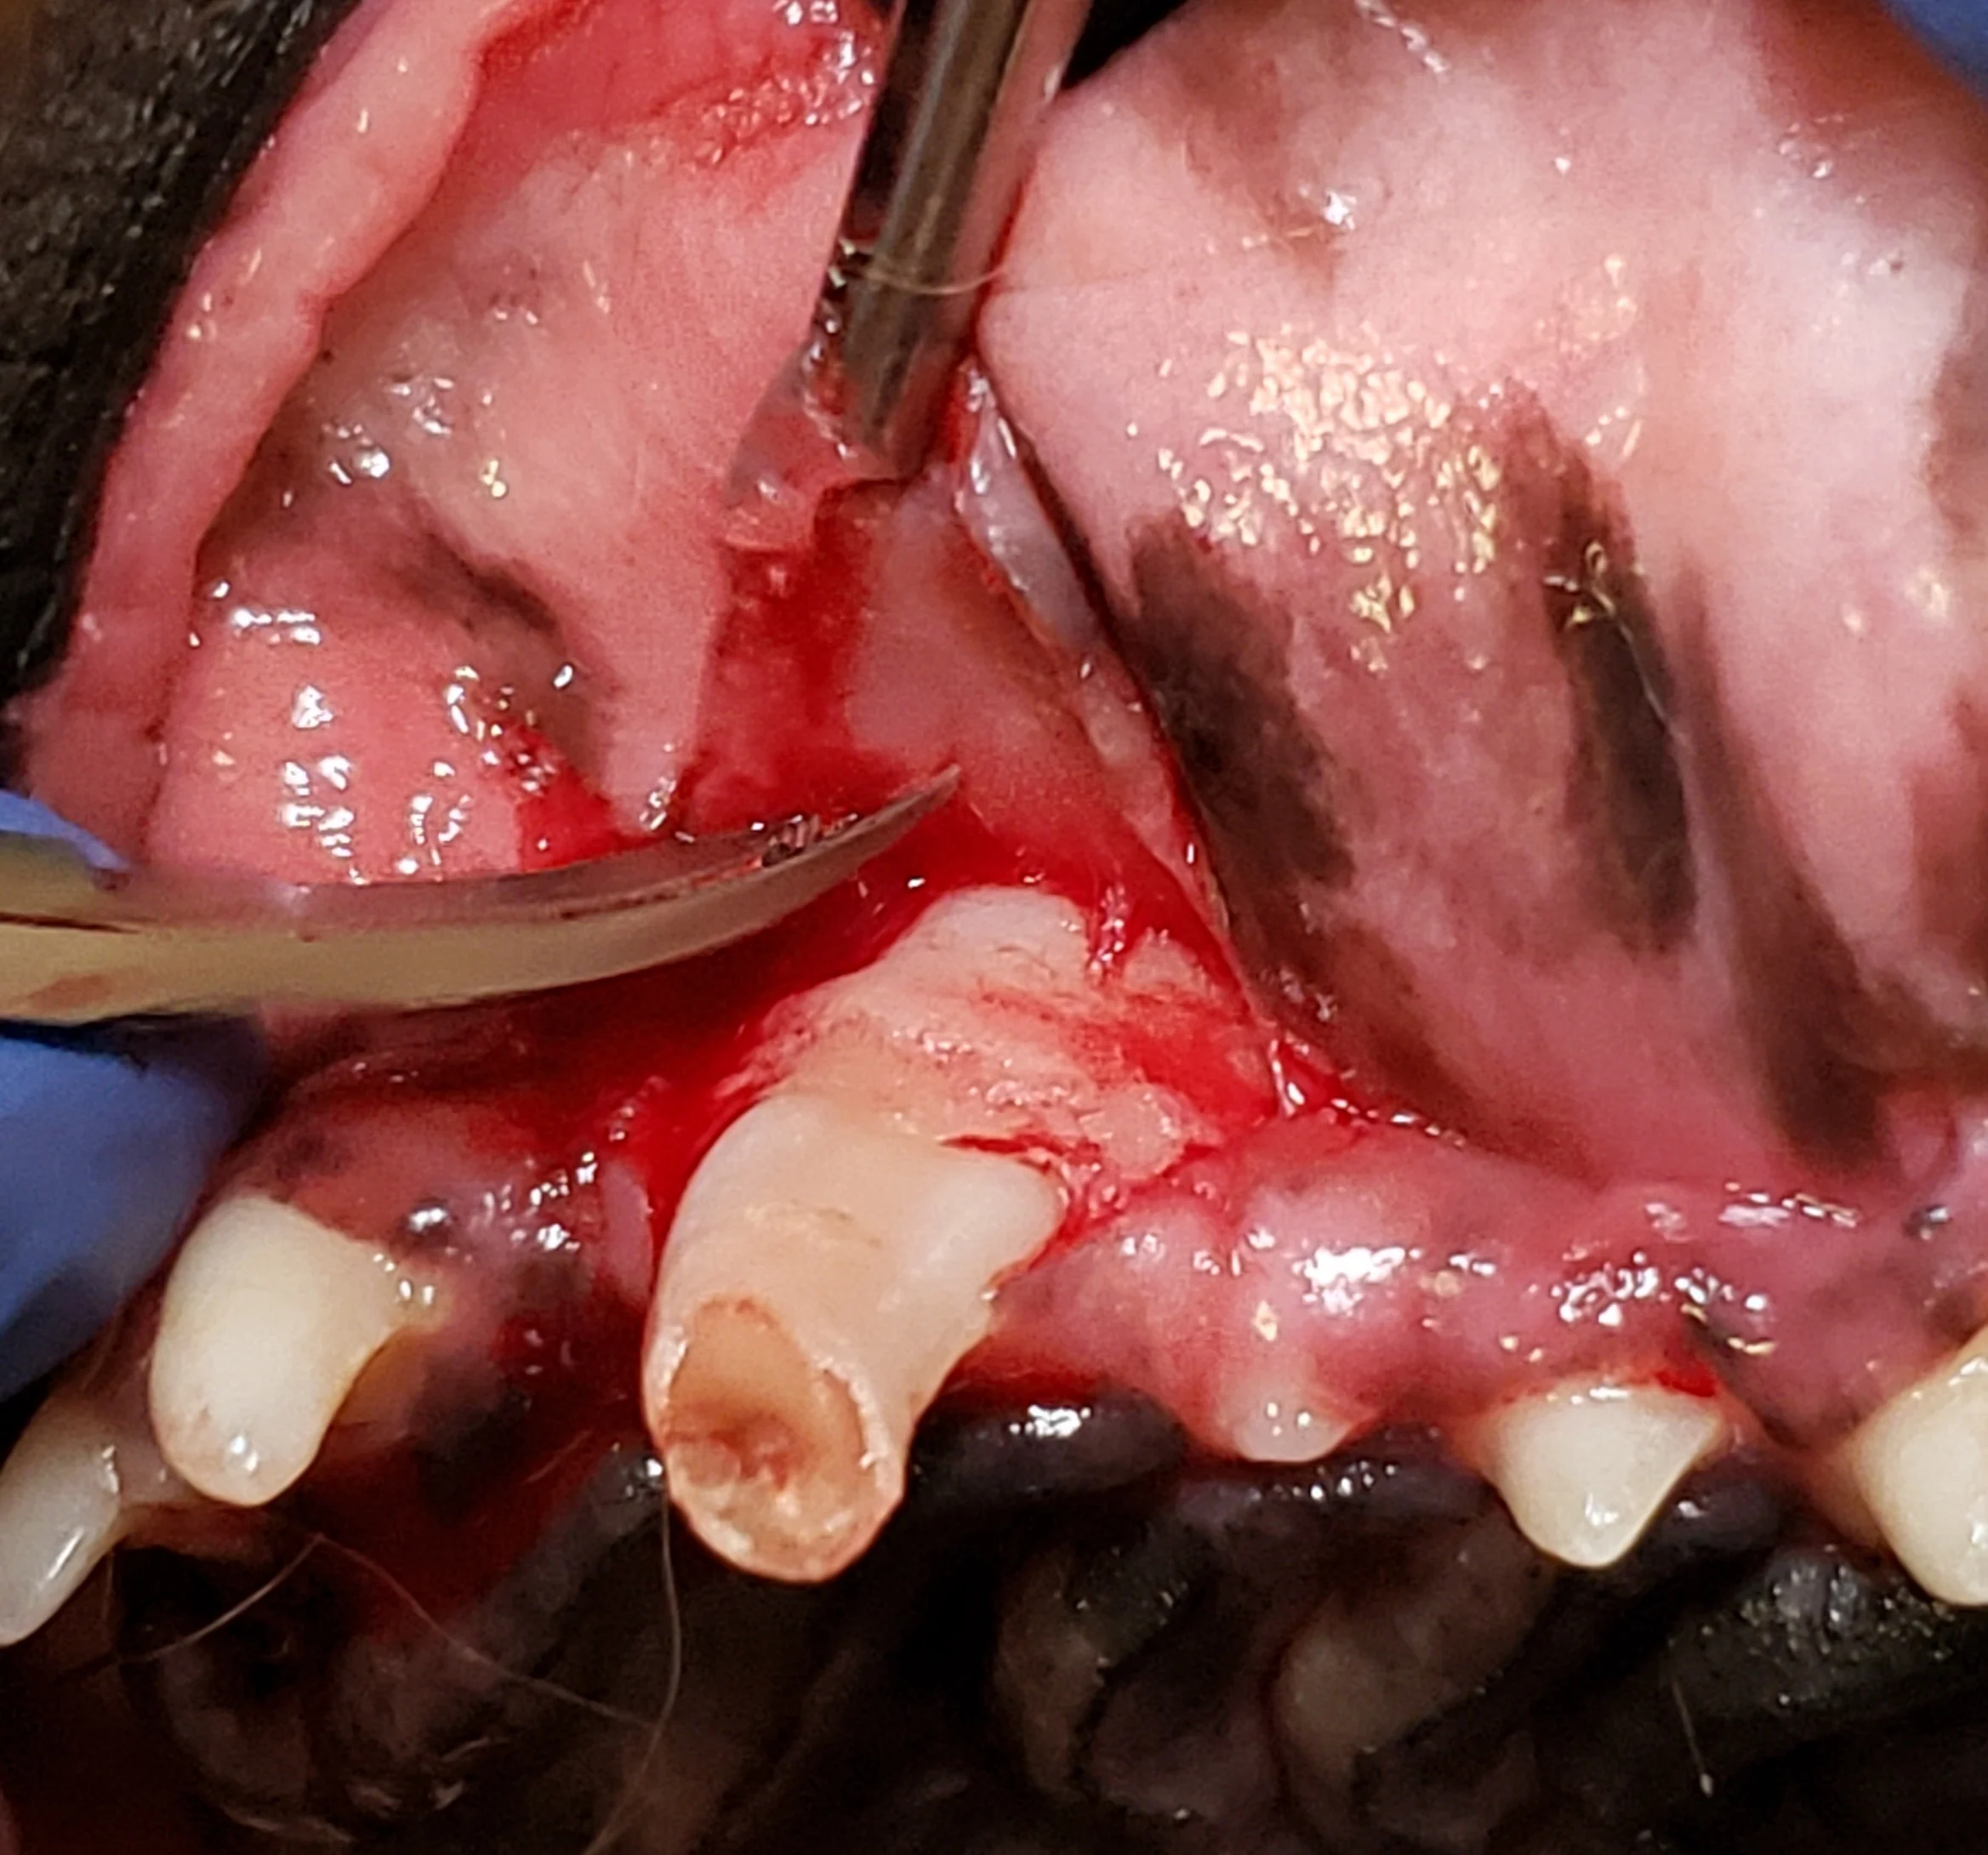

Step 7: Fatigue the Periodontal Ligament (Elevation)

Advance the blade edge of a winged elevator (sized appropriately for the diameter of the tooth root) using controlled apical force, with the tip of the elevator just past the fingertip grip. When positioned in the periodontal ligament space, rotate the elevator to engage the side or edge of the tooth surface, stretching the periodontal ligament. Apply slow, steady pressure for 5 to 10 seconds.

Author Insight

Although a rocking motion may be preferred over slow, steady pressure in some cases, this may result in a force that is not as effective, and care should be taken not to apply too much pressure. Winged elevators are primarily used on the mesial and distal aspects of maxillary canine teeth. If the entire crown is present, the curved portion may interfere with the ability to place the dental elevator in a straight line to access the distal periodontal ligament space. A portion of the crown may be removed to avoid this obstruction (dotted line).